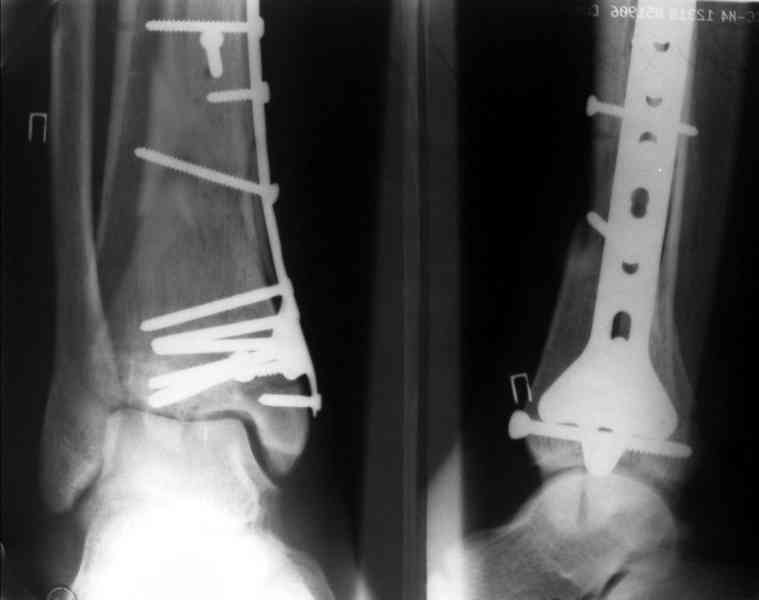

Послала ещё два снимка, если не пройдут, пошлю ещё. Дрягин. Если есть вопросы, готов ответить.

Посылаю результат лечения предыдущего больного через год.

С уважением Дрягин